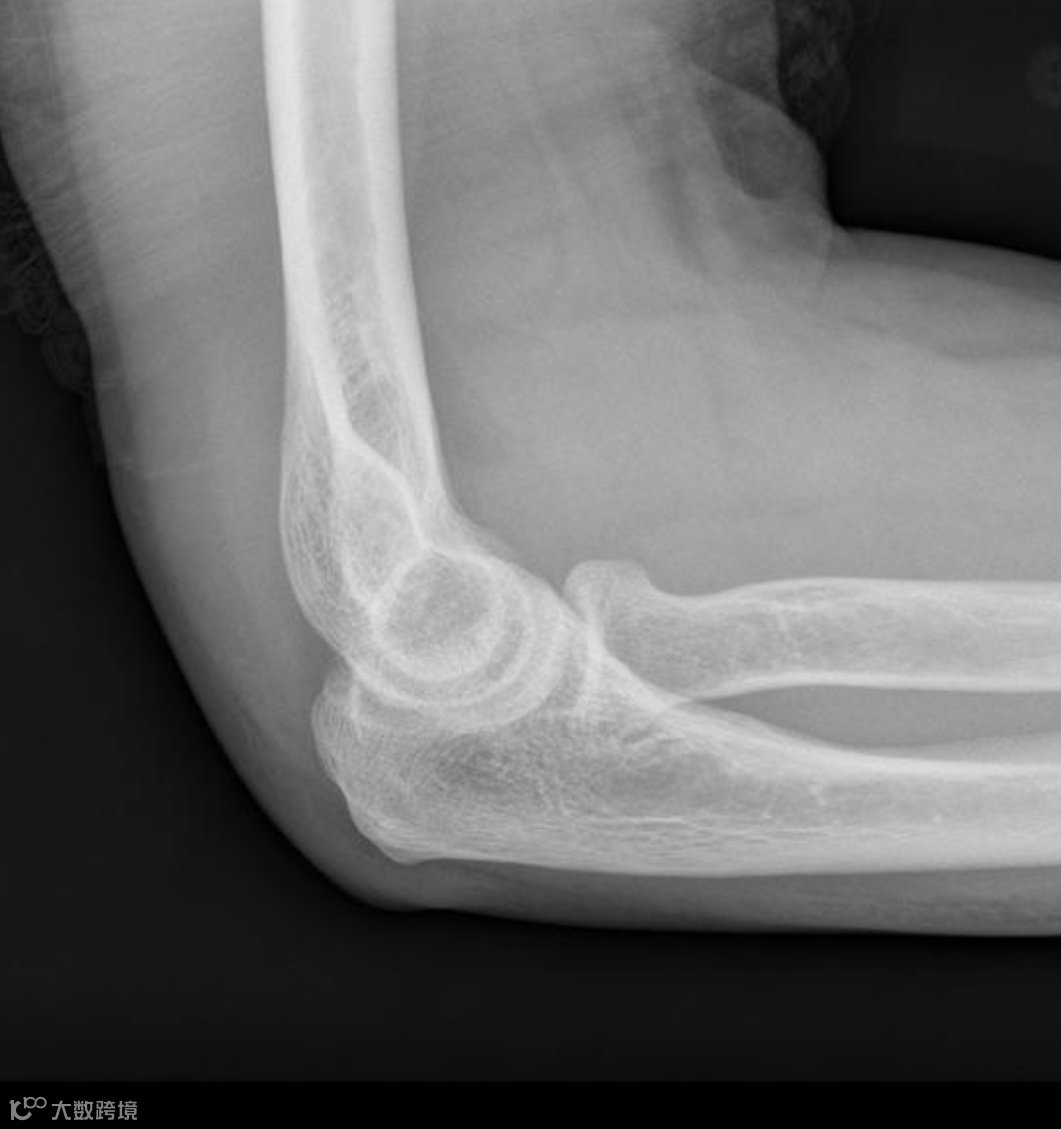

患者,女,30岁女子骑自行车摔倒,左肘着地,左肘关节正侧位X线示前、后脂肪垫征阳性(八字征),桡骨头外侧轮廓略显模糊,但未见明缺的骨折线。

同一患者,1周后复查,桡骨颈部可见一条细而模糊的硬化线,证实为桡骨颈骨折。

“前脂肪垫征阳性” 和 “后脂肪垫征阳性” 是提示外伤患者肘关节内存在隐匿性骨折的重要征象。同时出现时称为 “八”字征。若肘部受伤的儿童或成人患者,X光片上没有看到明确的骨折线,但出现了后脂肪垫征阳性(或前脂肪垫征明显的 “帆船征”),放射科医生应高度怀疑存在隐匿性骨折。